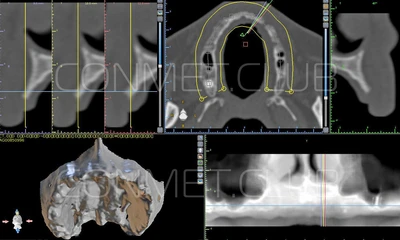

1. Пациенту было произведено МСКТ исследование нижней челюсти, с последующим созданием STL модели. В зуботехнической лаборатории был изготовлен восковой шаблон с искусственными зубами с учетом индивидуальных прикусных взаимоотношений (пока это делает зубной техник точно так же, как при изготовлении съемного пластиночного протеза).

2. После этого произвели компьютерное моделирование самого имплантата и фиксирующих элементов. Примечательно, что в абатментах, использовался отлично зарекомендовавший себя и проверенный десятилетиями интерфейс КОНМЕТ! В результате получили несколько специальных файлов, позволяющих не только сделать сам имлантат, но еще до операции изготовить и сами зубы. Данные файлы передали в изготовление на специальном 3D оборудовании.

В-третьих: современная субпериостальная имплантиация, хоть и сохранила основные черты своих предшественников, существенно изменилась в связи с применением цифровых технологий, начиная от цифрового КТ исследования, цифрового моделирования и заканчивая 3D печатью самого имплантата.